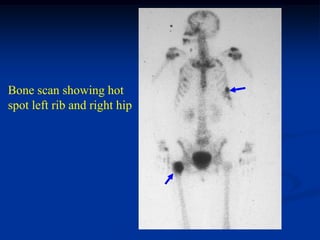

Case #1169

47 year female with stress fracture femoral neck looking like

a blastic metastasis

Bone scan showing hot

spot left rib and right hip

Photomic hip biopsy showing callous formation

Photomic showing callous formation

Post op bipolar prosthesis

because surgeon thought

patient had metastatic

disease when in fact the

femoral lesion and the

rib fracture are osteoporotic

pseudotumors